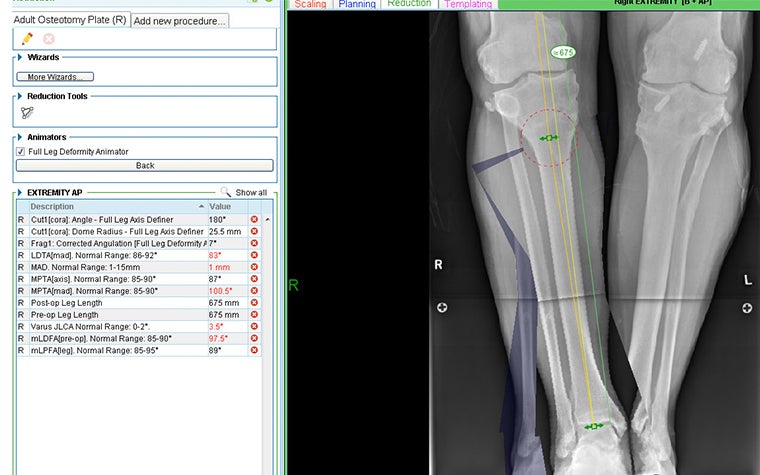

Using the axis definers in OrthoView’s LDC Module, a CORA was established which identified the magnitude of the angulation correction required as 18 degrees. A cut was added, a dome cut being preferred to an opening wedge as the latter would be too large and unstable in this case. An inverted dome cut was preferred over the standard orientation (as shown) to make it easier to avoid the patellar tendon.

On-screen ‘reduction’ identifies the following:

- No postoperative change in leg length

- An indication of the saw blade radius

- Location of where the mechanical axis passes through the knee joint. Note: Although medialized, this was judged to be acceptable.